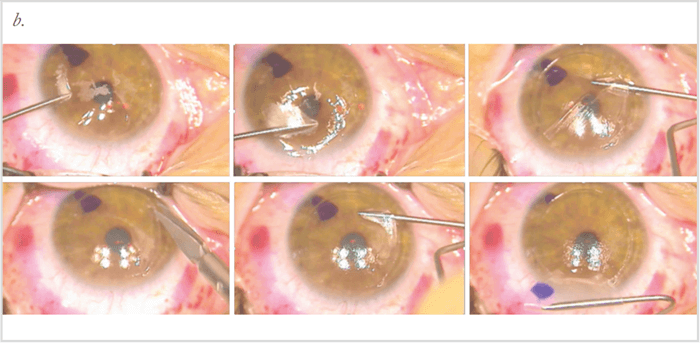

- Completing the case (Figure 1b); I started dissecting the flap on the side where I knew my raster pattern and side cut were normal. Coming from all angles, I was able to dissect carefully under most of the flap without issues. There was some incomplete dissection (about one clock hour) but I was able to complete the side cut with Vannas scissors. The stromal bed looked great and I was able to proceed with the case – and the patient had a great outcome.